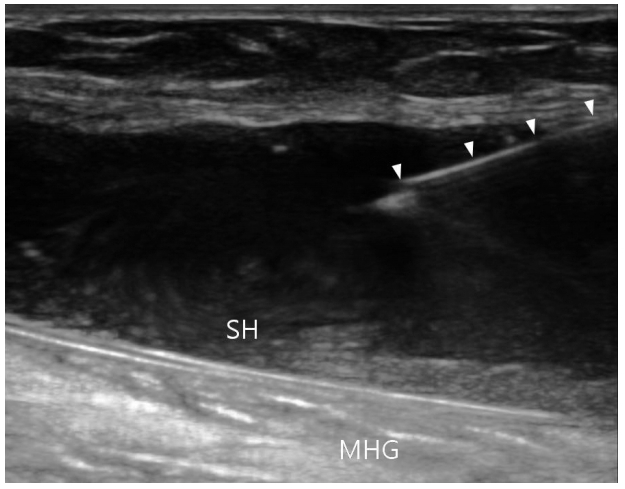

베이커낭종의 흡인과 스테로이드 주사를 할 때도 초음파는 유용하다. 슬와에 혹이 만져지는 경우, 베이커낭종 이외에도 슬와동맥류, 반월상연골낭종(meniscal cyst) 또는 정맥염이 원인인 경우도 있기 때문에, 천자를 하기 전에 초음파로 감별 진단을 하는 것이 안전하다. 낭종 내부에 활액막의 비후, 출혈, 석회, 유리체 등을 포함하고 있거나 낭종이 파열된 복잡한 경우에는 초음파 유도 없이 성공적인 흡인이 어려울 수 있다[25]. 환자를 엎드리게 한 후 슬와의 안쪽에 종축으로 탐촉자를 위치시키고 원위부에서 바늘을 진입시켜 바늘이 낭종 안에 들어가 있는 것을 확인 후 흡인한다(Fig. 10).